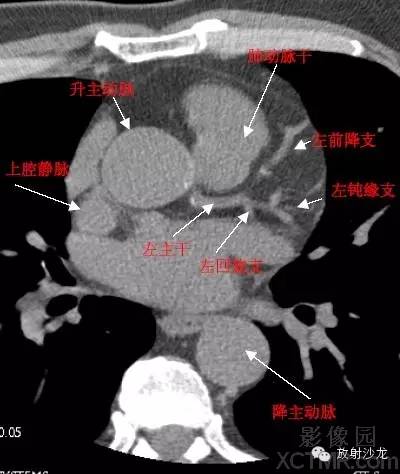

A.Aorta-Ascending Aorta升主动脉

D. Aorta-Descending Aorta降主动脉

SVC –Superior Vena Cava上腔静脉

PA -Pulmonary Artery肺动脉

LMA -Left Main Artery冠状动脉左主干

LAD -Left Anterior Descending Artery左前降支

LCX -Left Circumflex Artery左回旋支